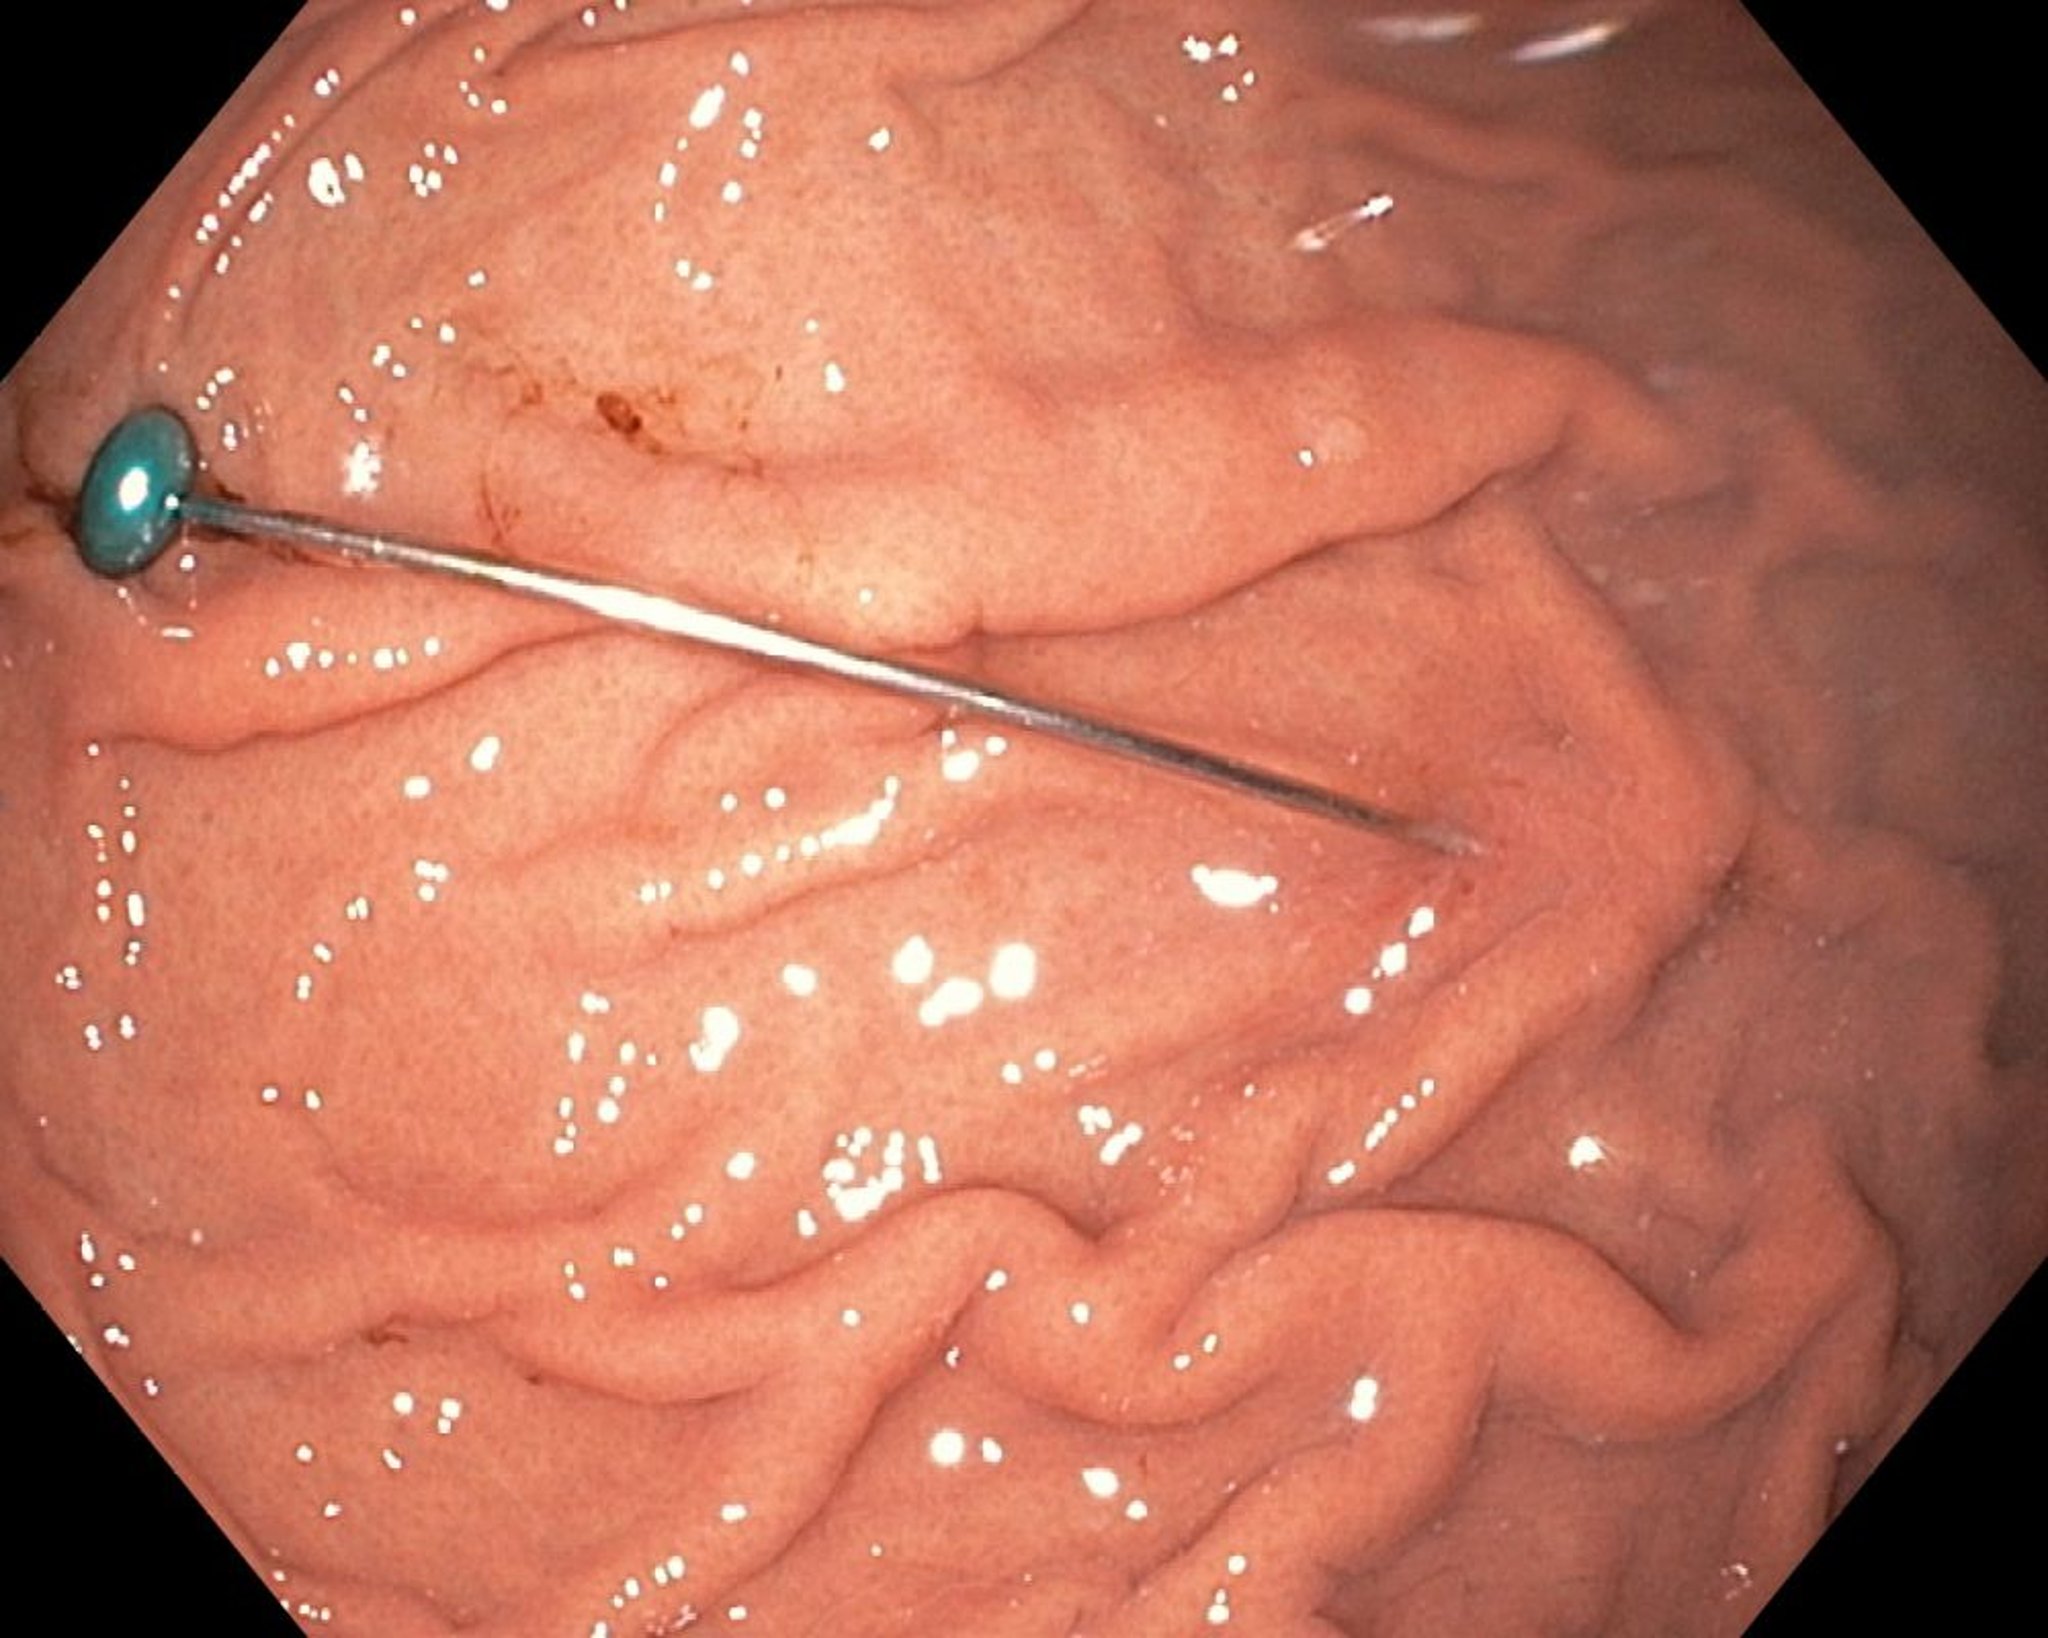

Esta imagen endoscópica muestra un cuerpo extraño punzante en el estómago.

Imagen proporcionada por Uday Shankar, MD.